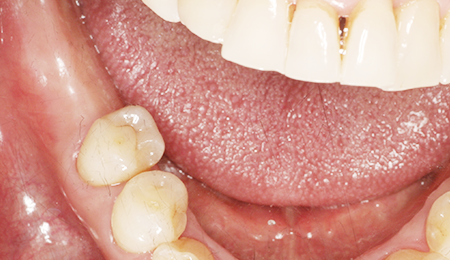

- BEFORE

- AFTER